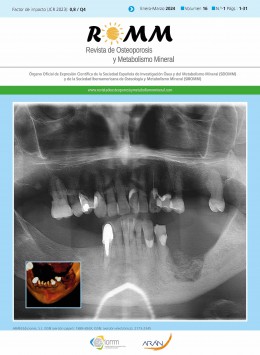

根據最新的數據,《Revista De Osteoporosis Y Metabolismo Mineral》雜志的IF影響因子為0.8。